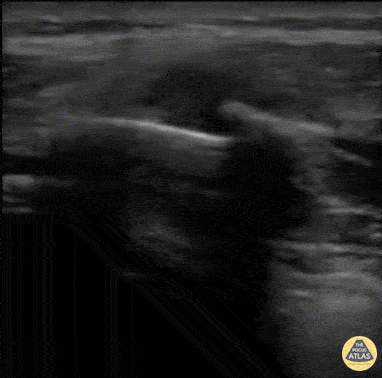

Musculoskeletal - Rib Fracture

40 y/o M with polysubstance abuse, left-sided rib pain after a traumatic blow. Chest xray was equivocal. The patient was asked to "point to where it hurt", and the linear transducer revealed a displaced rib fracture. He complained of significant pain even after the resident gave two Percocet and was unwilling to leave the ED. An intercostal nerve block, and that relieved the patient's pain and he went home. Dr. Stephen Alerhand, Mt Sinai Hospital NYC